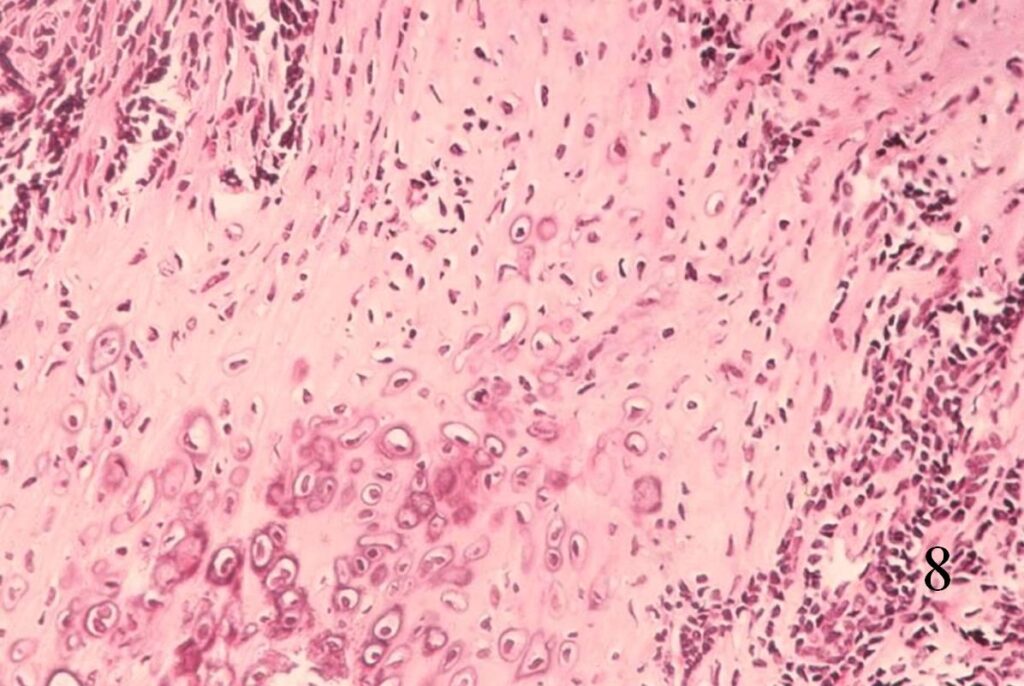

Extraskeletal Mesenchymal Chondrosarcoma (Fig. 8-10)

• Abundant small round blue cells

• Undifferentiated

• Round to elongate or spindle nuclei

• May grow in sheets or nodules, surround by fibrous tissue

• Usually proliferate around narrow vessels and pericytic sinusoidal vessels

• Islands of cartilage, may be calcified or ossified

Fig. 8

Fig. 8-10 Low (Fig. 8) and high power (Fig. 9) magnification of a mesenchymal chondrosarcoma shows cartilaginous areas and a mesenchymal component.